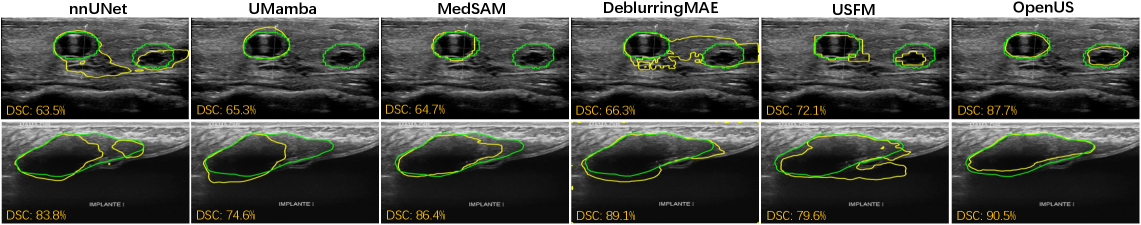

Refer to caption

Figure 4: Visualization of US segmentation results on TN3K and BUS-BRA. The ground truth is depicted in green, and the prediction is shown in yellow.

We visualize segmentation results in Fig. 4. Clearly, OpenUS outperforms other methods in accurately recognizing hazy tissue borders and demonstrates greater robustness to speckle in US images. Specifically, OpenUS demonstrates superior visual results in segmenting both large and small thyroid nodule regions (1st1^{st} rows in Fig. 4). We attribute these improvements to our self-adaptive masking strategy, which effectively captures more precise and clinically relevant details from US images. Similarly, OpenUS also exhibits strong performance in segmenting breast tumour (2nd2^{nd} row in Fig. 4).

Figure 9: Visualization of US segmentation results on TN3K and BUS-BRA. The ground truth is depicted in green, and the prediction is shown in yellow.

Fig. 9 demonstrates the segmentation results of our method and other superivised and self-supervised pre-training methods on the TN3K and BUS-BRA datasets. The results indicate that OpenUS outperforms other methods in the accurate recognition of indistinct tissue borders and demonstrates greater robustness to speckle noise in US images. Specifically, for thyroid nodule segmentation tasks involving noisy, low-quality US images (1st1^{st} and 3rd3^{rd} row in Fig. 9), nnUNet, UMamba, MedSAM, DeblurringMAE, and USFM inaccurately segment artefacts, whereas OpenUS remains robust. While some small thyroid nodules occupy very few pixels and are prone to omission (1st1^{st} row in Fig. 9), OpenUS successfully segments these challenging structures. In the breast cancer segmentation task (2nd2^{nd} row, Fig. 9), our method produces segmentation masks with smoother and more continuous edges. In contrast, other methods often yield results corrupted by speckle noise or containing inaccurate lesion boundaries.